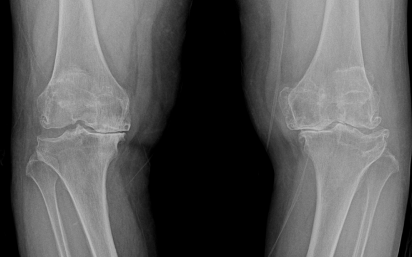

수술 전후 사례

수술 전

카티스템 수술

수술 후 1년

-